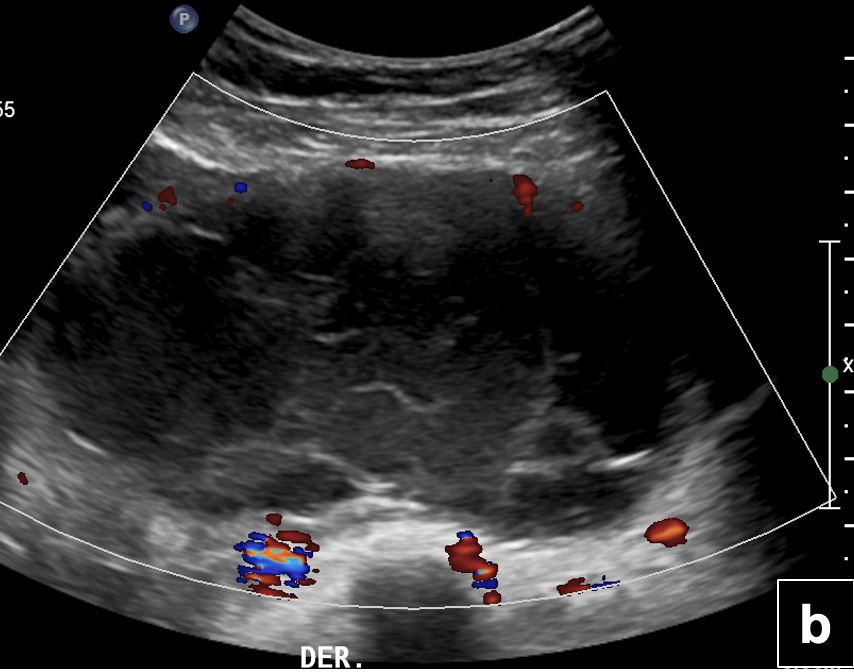

US de abdomen y pelvis: (a) Engrosamiento nodular solido del íleon distal (flecha) vascularizado al Doppler color, (b) el que se continua con imagen quística compleja de gran tamaño ubicada en la fosa iliaca derecha. (c) Engrosamiento parietal difuso de ileón distal visualizado con transductor de alta frecuencia (flecha)